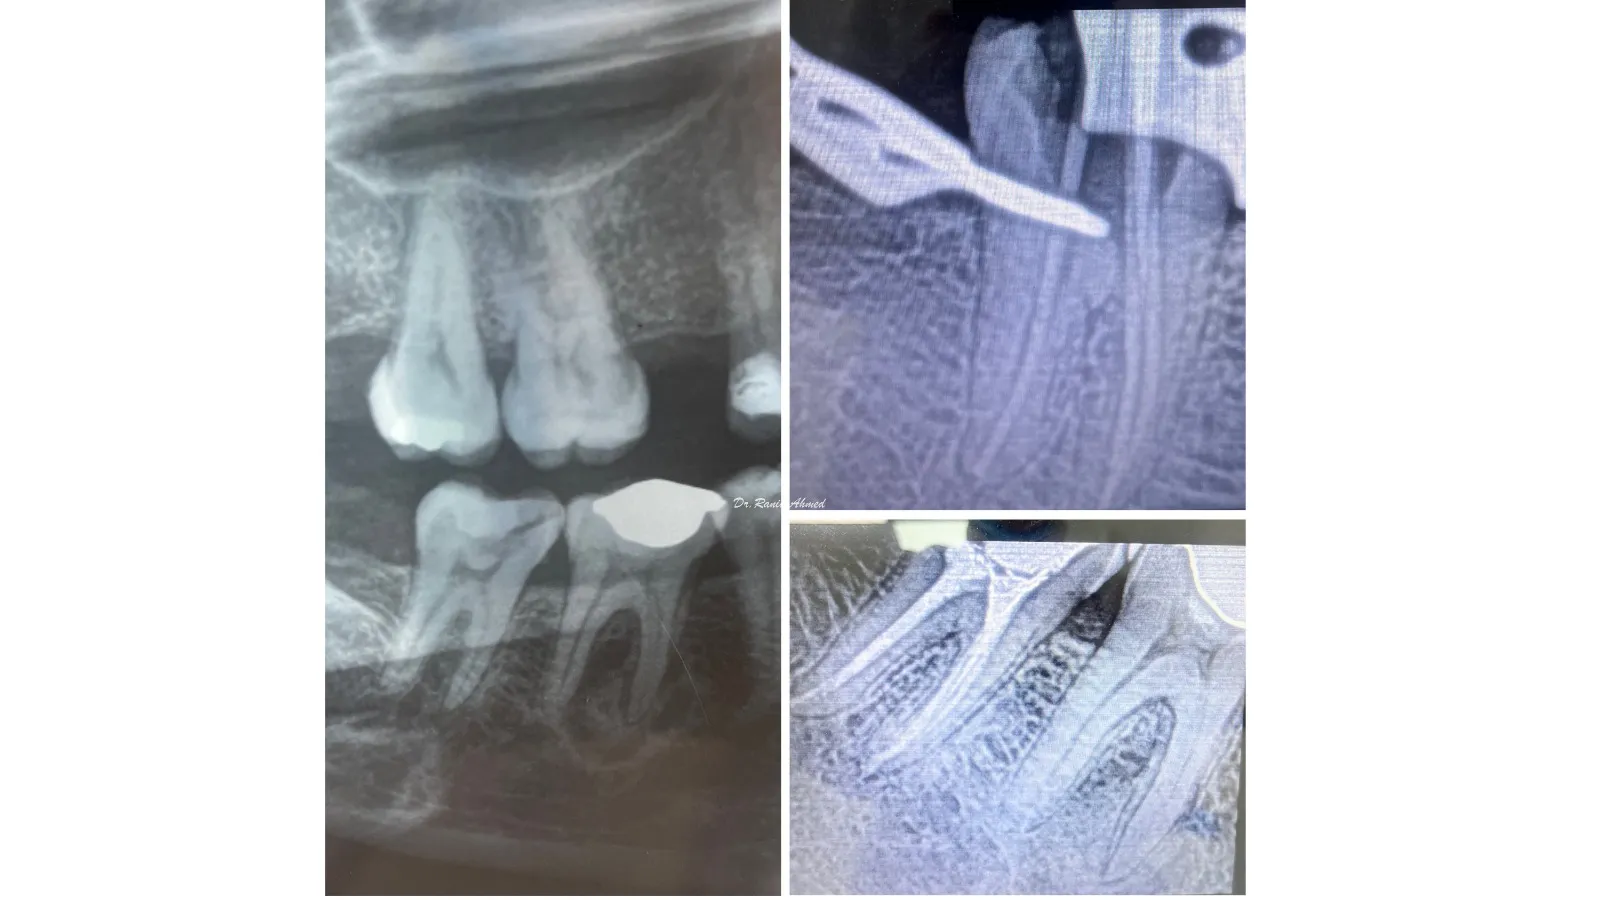

Endodontic Treatment